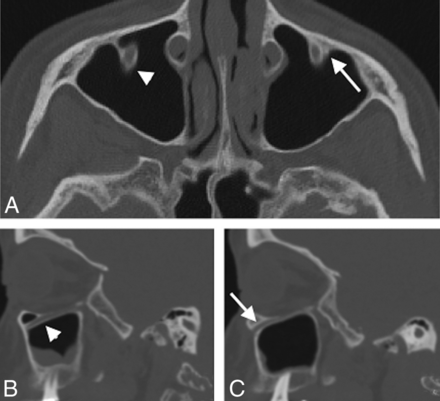

Coronal (A), axial (B), and right parasagittal (C) CT images in a 58-year-old man show bilateral protrusion of the IOC into the maxillary sinus. On the coronal image, an infraorbital ethmoid (Haller) cell is seen on the right (arrowhead) just medial and superior to the protruding IOC (arrow). Bilateral protrusion is seen on the axial image (arrows), and confirmation of protrusion is seen on the sagittal image through the right maxillary sinus. The presence of a protruding IOC near an infraorbital cell is important for the endoscopic surgeon to know preoperatively, in the event that the infraorbital cell is targeted during sinus surgery.